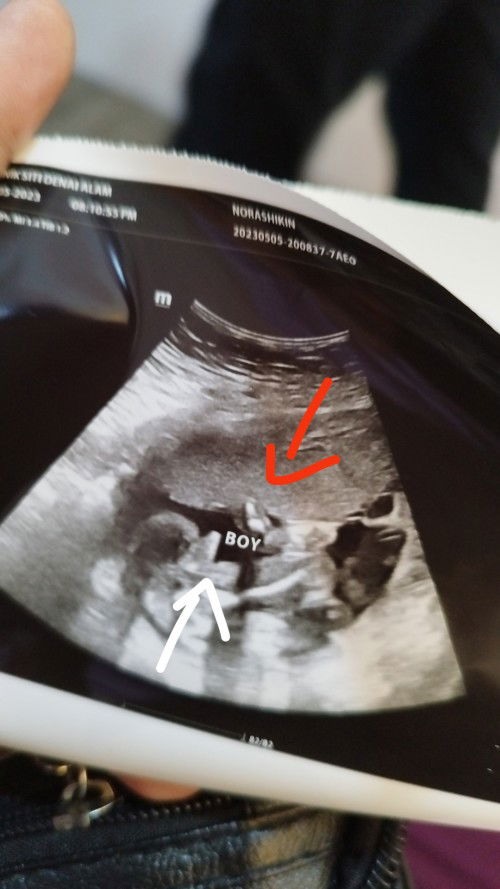

Nk tanya btul ke boy pastu mana satu alat kelamin nya saya tgok mcm yg atas tu

Yg panah merah tu ke kelamin nya atau yg putih doktor ckp boy